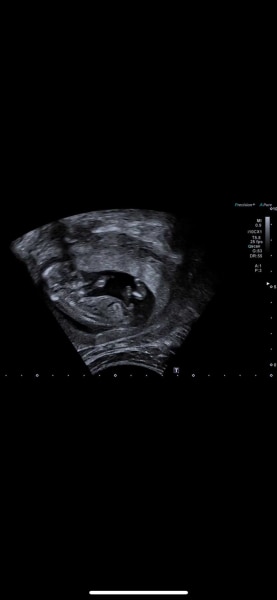

Hi, was vermutet ihr? Mädchen oder Junge? Eine Tendenz wurde von der Gyn heute abgegeben...

Bild zu Mädchen oder Junge? :-) - Schwanger - wer noch? Rund um die Schwangerschaft

Huhu Mrsr, ich hab deine Bilder gerade glaube ich Gefühl 20 mal angeguckt und bin neugierig, was du für eine Tendenz bekommen hast.  Meine Vermutung wäre ein Junge.  Beim ersten Bild steht es ein bisschen nach oben und auf dem Nub ist noch eine kleine Wölbung.  Das zweite Bild find ich persönlich schwierig zu beurteilen, weil das Baby dort ein bisschen zur Seite gedreht ist .Da ist der Nub gerader, was wiederum eher für ein Mädchen sprechen würde. Allerdings ist der Nub recht dick, was mich irritiert (könnte aber auch einfach dicker wirken, weil das Baby gedreht ist und man den Nub und oben drauf die Wölbung zusammen auf ein Bild bekommen hat 🙆‍♀️...  Für ein Mädchen Nub fehlt halt diese Typische Gabelung... je mehr ich schreibe merke ich dass ich immer mehr zum Baby Boy tendiere.  LG Cleo

ja uns wurde Junge gesagt....